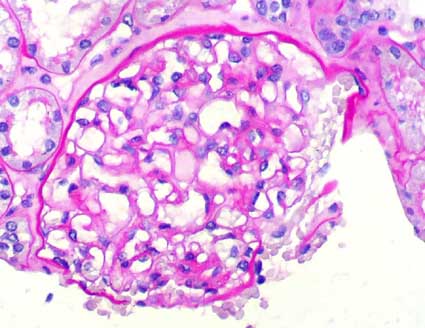

Figure 3.

PAS stain, X400.